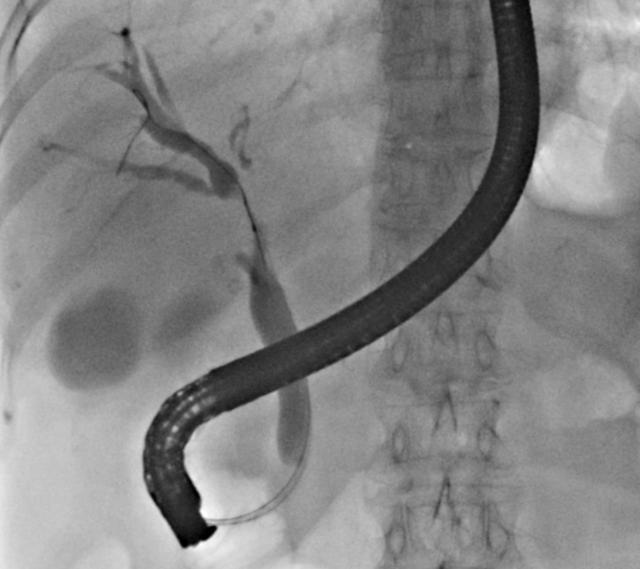

经内镜方式放置胆道支架是在介入手术室DSA机引导下,用十二指肠镜从口经食管到达胃,至十二指肠乳头处,通过十二指肠镜逆行插管至胆管内,放入塑料支架或金属支架。

放射介入下放置胆道支架是在DSA机下,经穿刺进入胆管,在X线引导下,通过特制导丝越过肿瘤狭窄段,使支架越过肿瘤位置,达到引流目的。